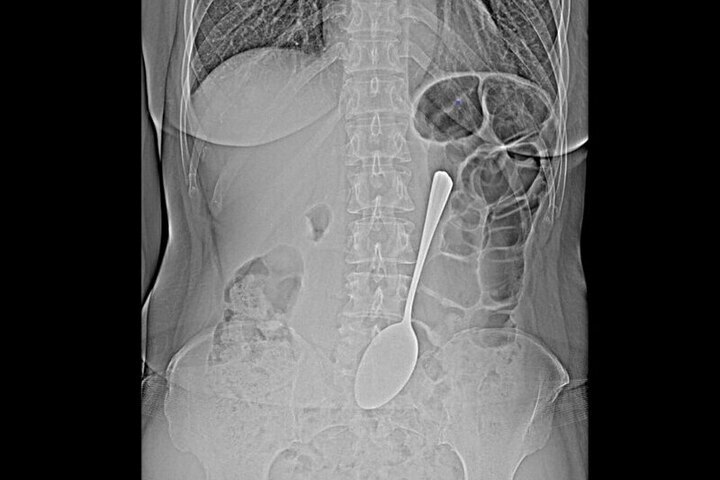

Инородный предмет успешно извлекли из желудка с помощью эндоскопа и специальных инструментов. Эта современная методика позволила избежать сложной полостной операции, которая потребовала бы длительного восстановления, пояснили в БСМП.

После успешно проведенной эндоскопической процедуры пациентку выписали. Мотивы, по которым женщина проглотила столовую ложку, остались неизвестны — она не стала их объяснять врачам.